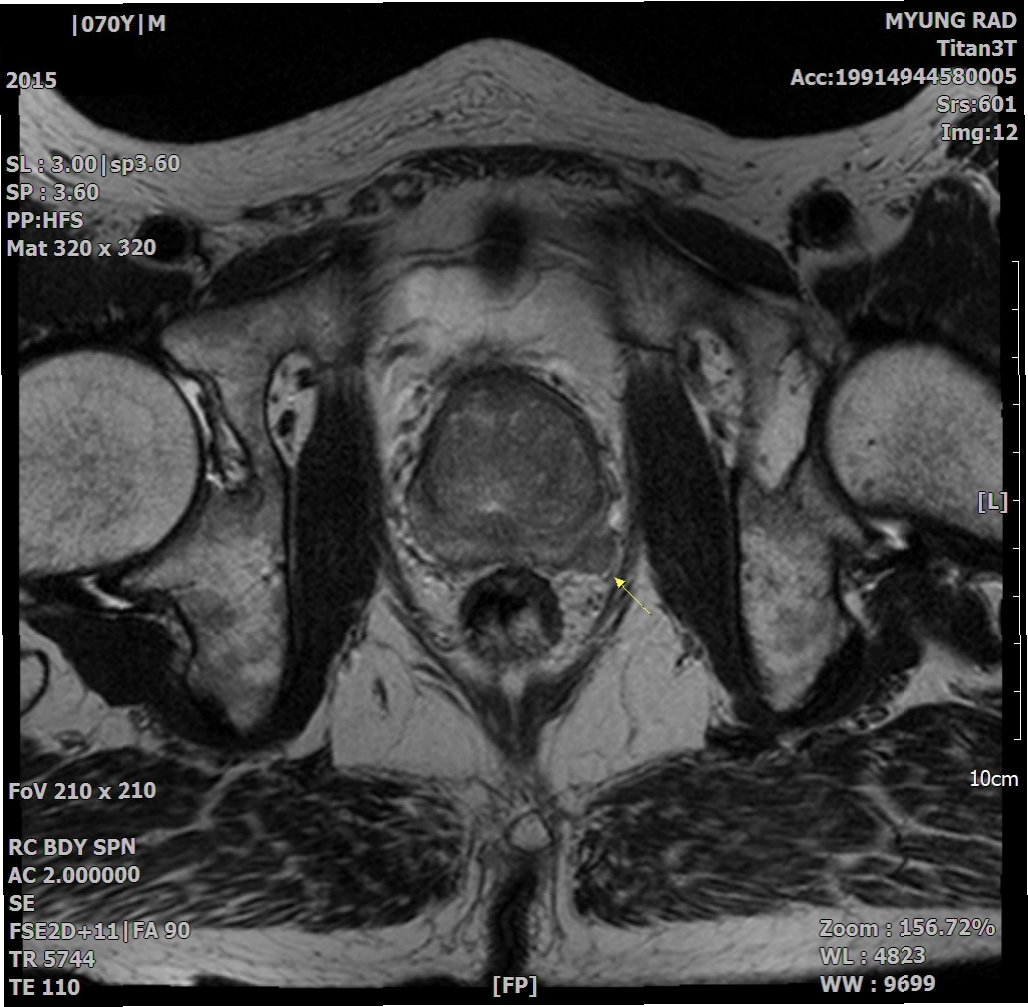

전립선암 진단은 PSA(전립선 특이항원) 혈액 검사를 통해 시작됩니다. PSA 수치가 높게 나타나면 MRI 촬영을 통해 암 의심 부위를 확인하고, 조직 검사를 통해 확진합니다. 치료 방법으로는 수술적 치료와 약물 치료가 있습니다. 수술은 전립선과 정낭을 제거하는 과정이며, 약물 치료는 남성 호르몬을 차단하여 암의 성장을 억제하는 것을 목표로 합니다. 조기 진단과 적절한 치료가 중요합니다.